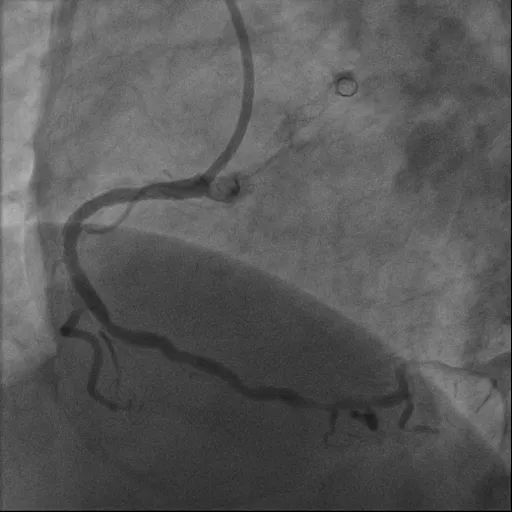

造影检查显示:冠状动脉三支病变。其中,右冠状动脉近中段狭窄钙化最重处约 90%,伴重度弯曲;左冠状动脉前降支近中段狭窄钙化最重处约 85%;左冠状动脉回旋支近段狭窄约 85%。

术中,充分预处理 Shockwave 球囊后,沿导丝推送球囊至钙化病变血管段,扩张球囊后,释放冲击波。经多次单轮操作,逐一击碎「坚如磐石」的钙化病变,成功置入支架。

造影可见血管狭窄明显缓解,管腔面积得到有效恢复,血流通畅。